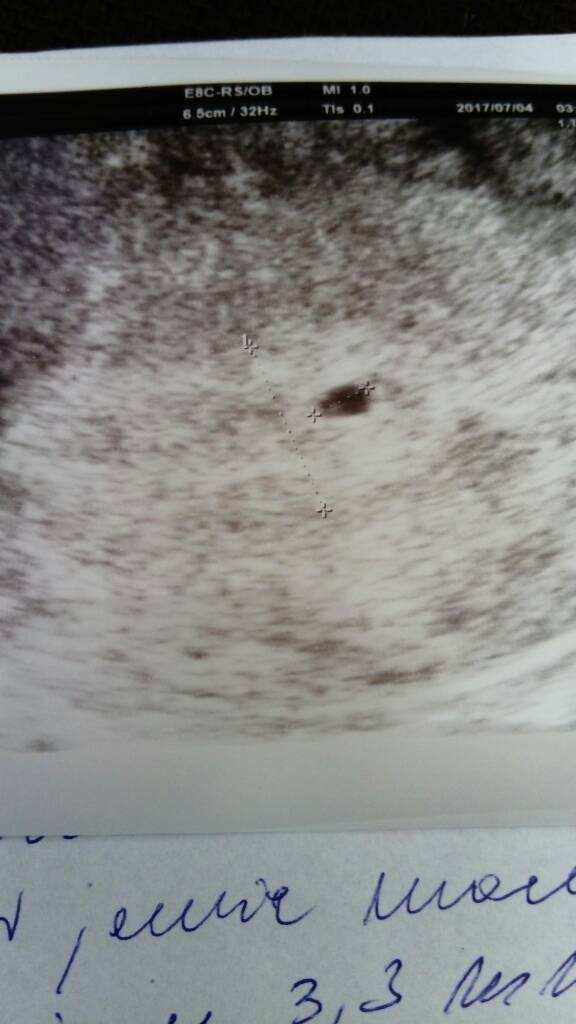

Oj Kochana to masz ładniutką betę. Musiałam mieć szybką owulacje. Także pęcherzyk ciążowy raczej napewno powinnaś jutro zobaczyć, a czy zarodek to trochę wątpliwe, ale lekarzem nie jestem[emoji12][emoji12][emoji12]Będę trzymać mocno kciuki!!! Ja też jutro ale o 7.45 [emoji6][emoji6][emoji6] Ja liczę na zarodek bo na serduszki chyba jeszcze ciut za wcześnie 5t7d jutro.4 tydzień 3 dzień. Nie wiem kiedy miałam owulacja. Na jutro zapisałam się na usg na 17.40 także trzymajcie kciuki :-)